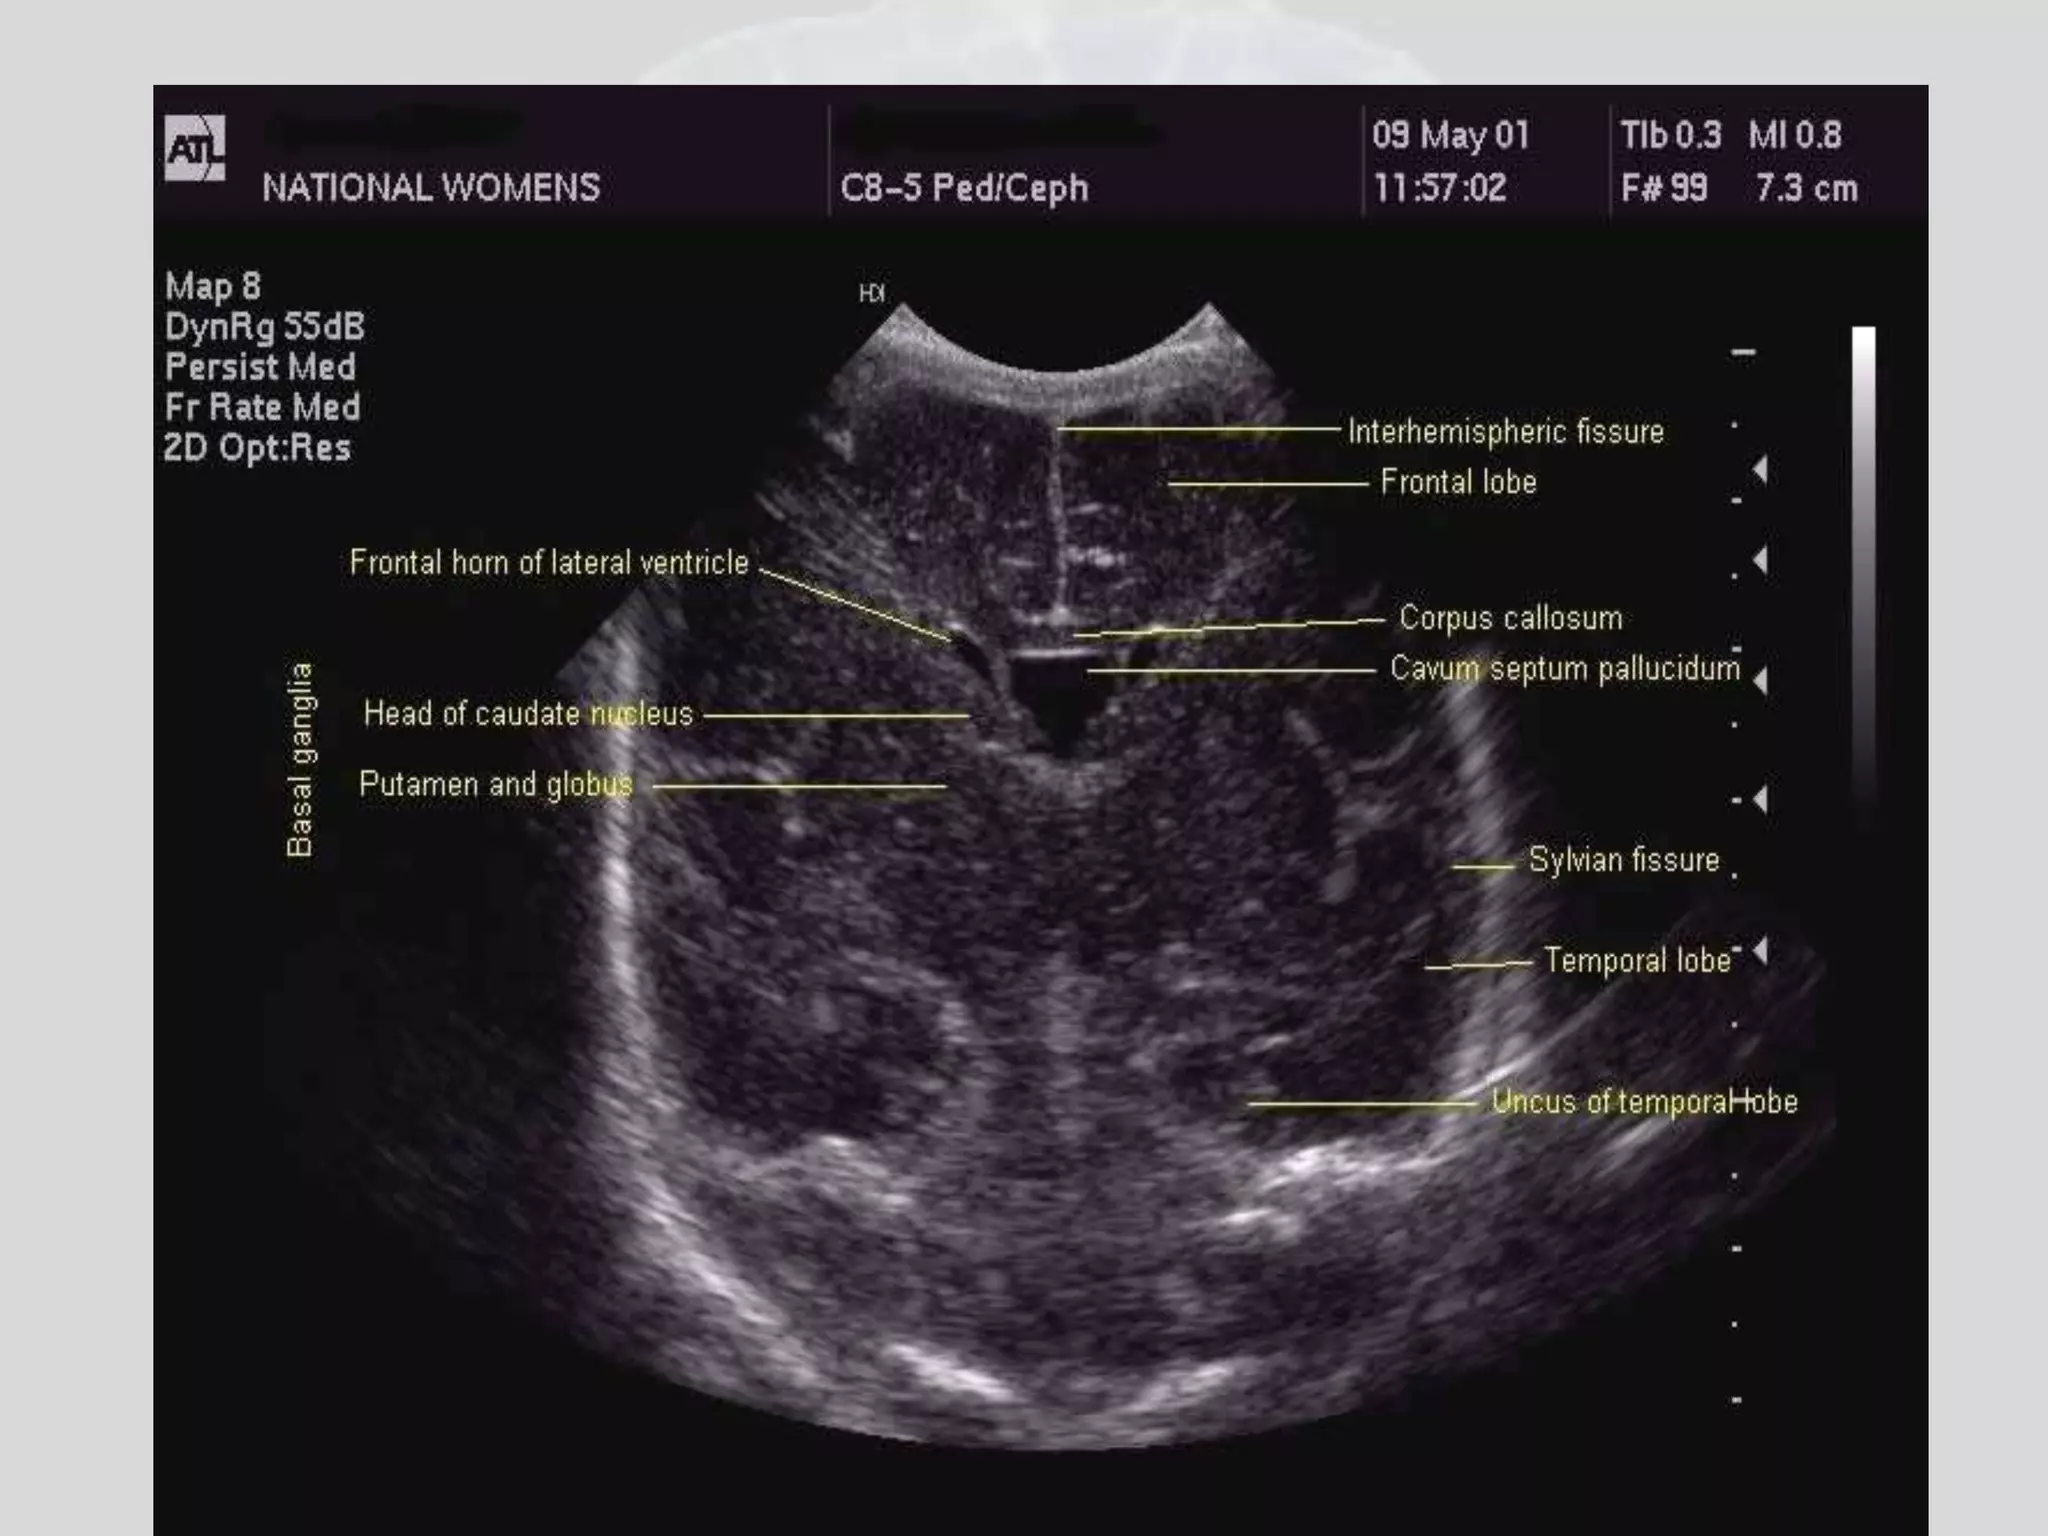

Cranial usg coronal view frontal lobe

Cranial usg coronalview frontal lobe